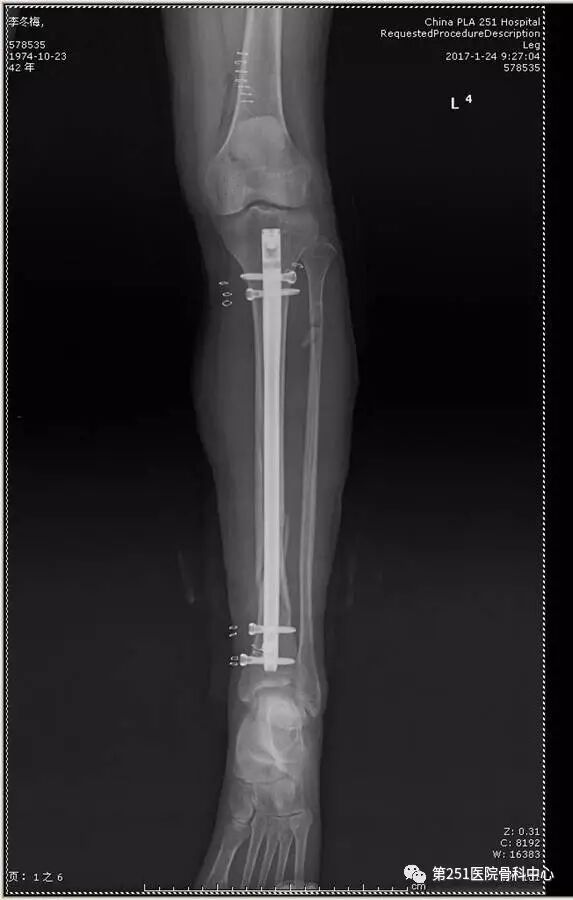

病例2:男性,44岁,车祸伤,双侧胫腓骨骨折(左侧)。